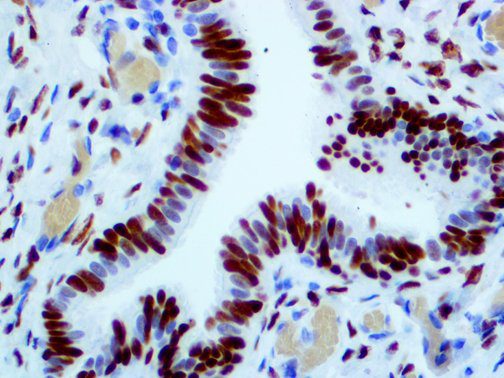

It is the ICU physician who is most likely to witness one of the deadliest manifestations of the abnormal immunological response, the cytokine storm syndrome (CSS). This response is also referred to by some as the cytokine release syndrome (CRS). CSS is characterized by continuous activation and expansion of macrophage and lymphocyte populations, which secrete large amounts of cytokines, causing the cytokine storm. This massive cytokine release is akin to hemophagocytic lymphohistiocytosis (HLH) disease, a syndrome characterized by initial unchecked and persistent activation of cytotoxic T lymphocytes and NK cells.

Clinical and laboratory manifestations of HLH include fever, enlarged liver and/or spleen, neurologic dysfunction, coagulopathy, liver dysfunction, cytopenias (i.e., low levels of erythrocytes, leukocytes, and/or platelets), hypertriglyceridemia, hyperferritinemia, hemophagocytosis, and eventually diminished NK cell activity as the immune system becomes progressively paralyzed. HLH can be familial (primary HLH) or secondary to another disease process (sHLH), such as rheumatic disease, in which it is referred to as macrophage activation syndrome (MAS, characterized by elevated ferritin).